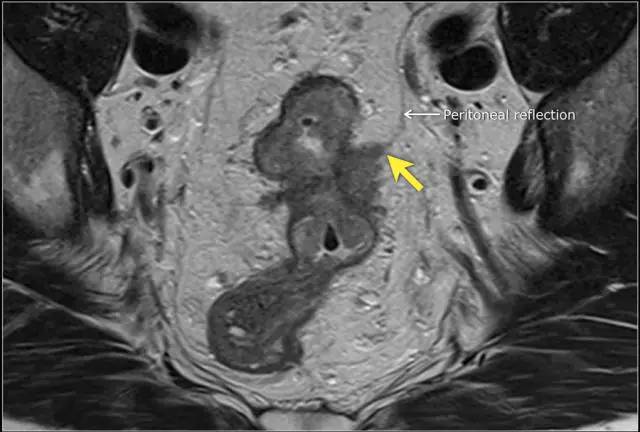

低直肠完全被直肠内筋膜覆盖。在直肠中部,其后侧和外侧由直肠内筋膜覆盖,但在前侧由内脏腹膜覆盖。内脏腹膜生长意味着扩散到腹膜腔。在矢状 T2 加权图像上,腹膜反折可以描绘为连接膀胱与直肠前后方面的低信号细线。

图 14 轴向 T2 加权图像上,沿着内脏腹膜有肿瘤向内生长(箭头)

图 15 同一患者腹膜转移的矢状图(箭头),在直肠内还有可疑的淋巴结